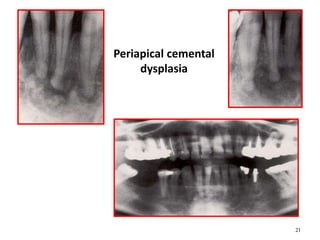

R.L R.L+R.O

21

Periapical cemental

dysplasia

22

Periapical Cemental Dysplasia